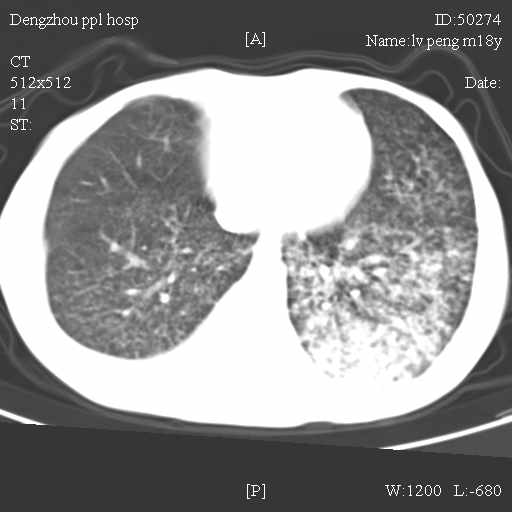

标题: CT10510:男.18岁,咳嗽咳痰两月.(有病理) [打印本页]

标题: CT10510:男.18岁,咳嗽咳痰两月.(有病理)

双肺布满大片状实变及网格状结节影,内参杂大小不等的气囊及空气支气管征,心脏增大。考虑:1 全身结缔组织疾病—系统性红斑狼仓?2 肺泡蛋白沉积症合并感染!

双肺布满大片状实变及网格状结节影,内参杂大小不等的气囊及空气支气管征,双侧胸膜腔少量积液,双下肺近膈面透亮度尚可,病人较年轻,病变较重(不知为什么上胃管?)考虑:1.胶原病肺部改变,2.组织细胞病x。结合实验室检查。

首先考虑组织细胞x病。两肺中上肺野多发囊腔,中下肺野内见多发小结节,并可见肺间质增厚。患者是男性,年龄较小。胶原性病变比较多见的类风湿、系统性红斑狼疮和硬皮病临床和影像均不是很支持,类风湿和系统性红斑狼疮的肺部表现最常见的是胸腔积液,硬皮病可见食管的扩张。

肺内多发斑片状、结节状、融合大片状及网格状影,多发薄壁空腔影,胸膜肥厚,纵隔、气管右移,考虑ⅲ型肺结核,多发空洞,继发肺间质纤维化。

双肺结核并播散.患者以肠梗阻入院,手术为肠结核.术后咳嗽做ct检查.